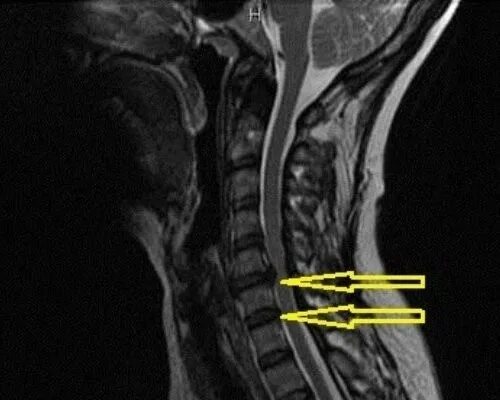

Протрузия диска с3 4